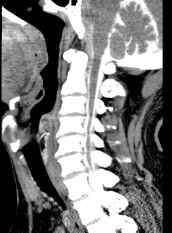

术前脊髓造影后CT,明显可见脊髓压迫